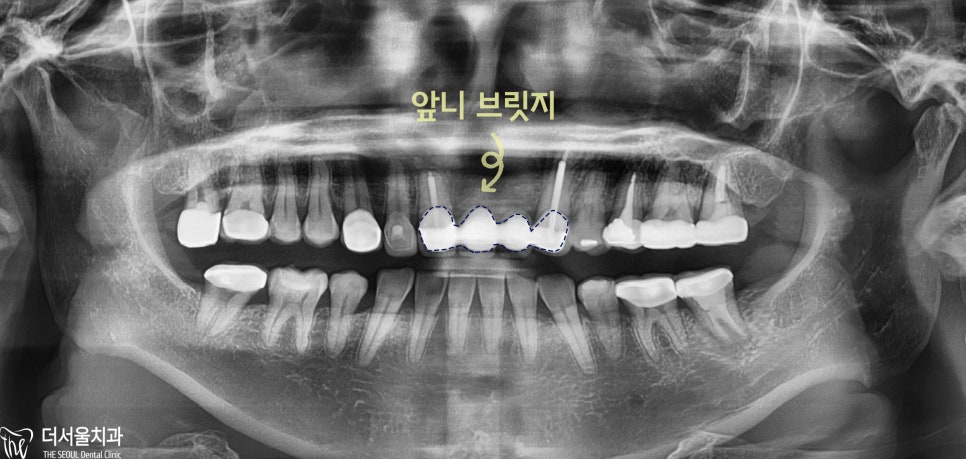

오늘 소개해 드릴 환자는

젊은 여성분으로

브릿지 가 마음에 들지 않아요.

라는 주소로,

더 서울 치과 를 내원해 주셨습니다.

오래전에

앞니 브릿지 치료를 받았는데

인위적인 느낌이 드신다고 말씀하셨습니다.

기존에

브릿지 를 제거하고

인공치[Pontic] 부분에 픽스쳐를 식립했습니다.

치근단 사진을 보면

총 2개를 심은 것을 알 수 있으며

힐링어버트먼트로 체결한 것을 볼 수 있었습니다.